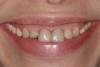

Fig 20. Extraoral view of final result; note the marked reduction of the gummy smile.

Figure 20

The temporary crowns were replaced with single crowns, and porcelain veneers were used on the upper laterals and canines (Figure 20). Knife-edge preparations were used for the final restorations as they were situated on radicular surfaces of the teeth, though this would affect the adhesion of the restorations.15